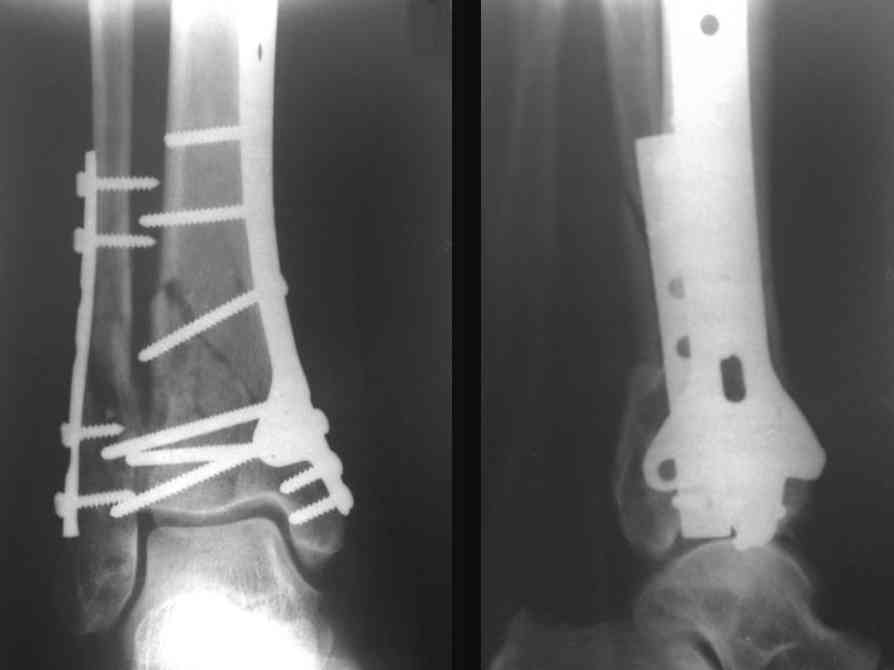

Послала ещё два снимка, если не пройдут, пошлю ещё. Дрягин. Если есть вопросы, готов ответить.